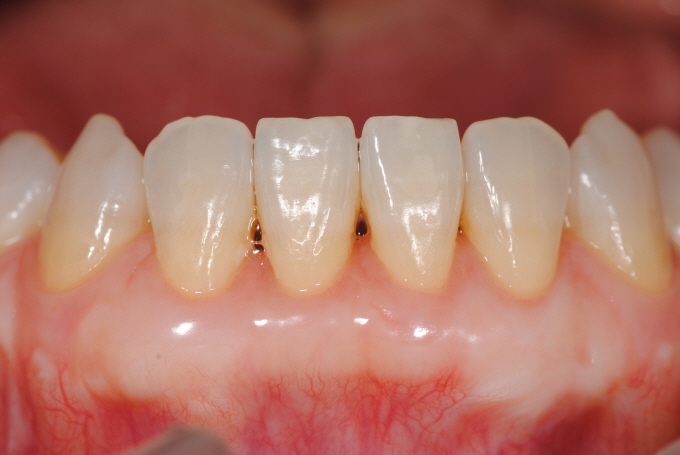

| Fig. 4&5&6: 48¼¼ ¿©ÀÚ, ¿À·£ ½Ã°£À» µé¿©¼ ±³Á¤Ä¡·á¿Í º¸Ã¶Ä¡·á¸¦ ÀüºÎ ¸¶Ãưí, ³²¾ÆÀÖ´ø Marginal migration of gum tissue with hypersensitivity ¹®Á¦¸¦ Subepithelial C.T. graft procedures ·Î¼ Àß ÇØ°áÇÒ ¼ö ÀÖ¾ú´Ù. 2016³â 1¿ù¤·ÀÏ ÇϾÇÁÂÃø Á¦ 2 ´ë±¸Ä¡ ¼³Ãø ±×¸®°í »ó¾ÇÁÂÃø Á¦ 1 ¼Ò±¸Ä¡¿¡ ´ëÇÏ¿© MG plastic surgery¸¦ ÇÏ¿´°í, ÀÌ¾î¼ 2¿ù¤·ÀÏ ÇϾÇÀüÄ¡ºÎ |